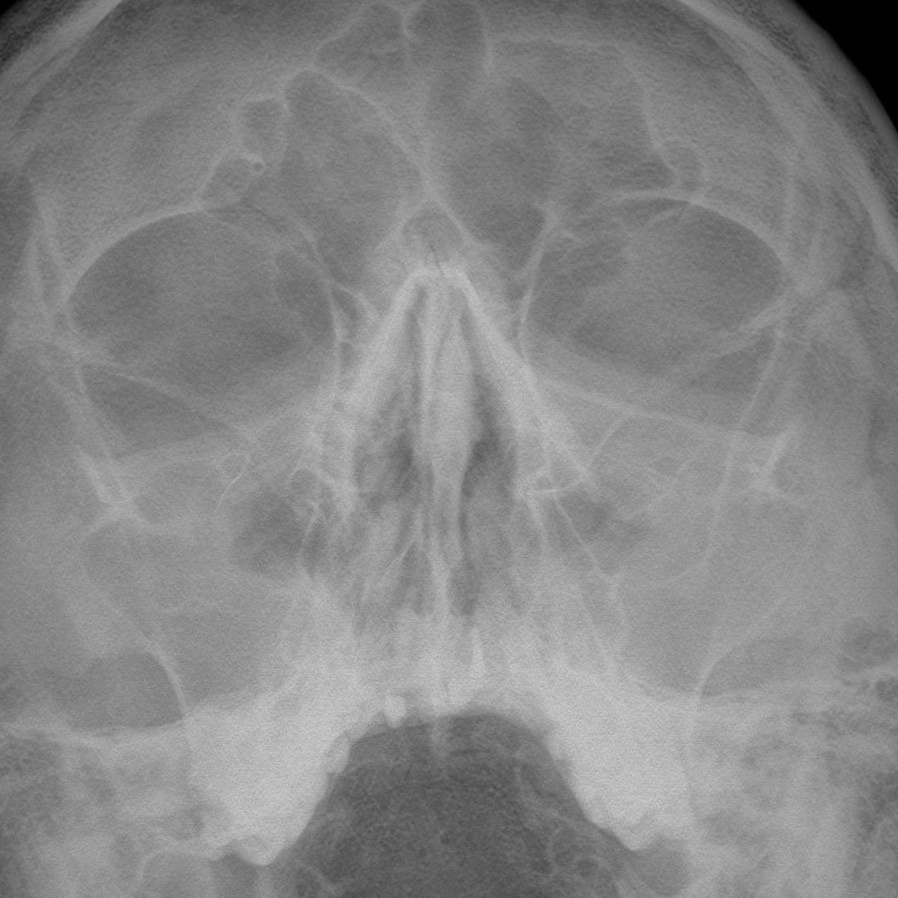

Этот вопрос ставит в тупик не только пациентов, но и бывалых терапевтов, гастроэнтерологов, лор-врачей и многих...